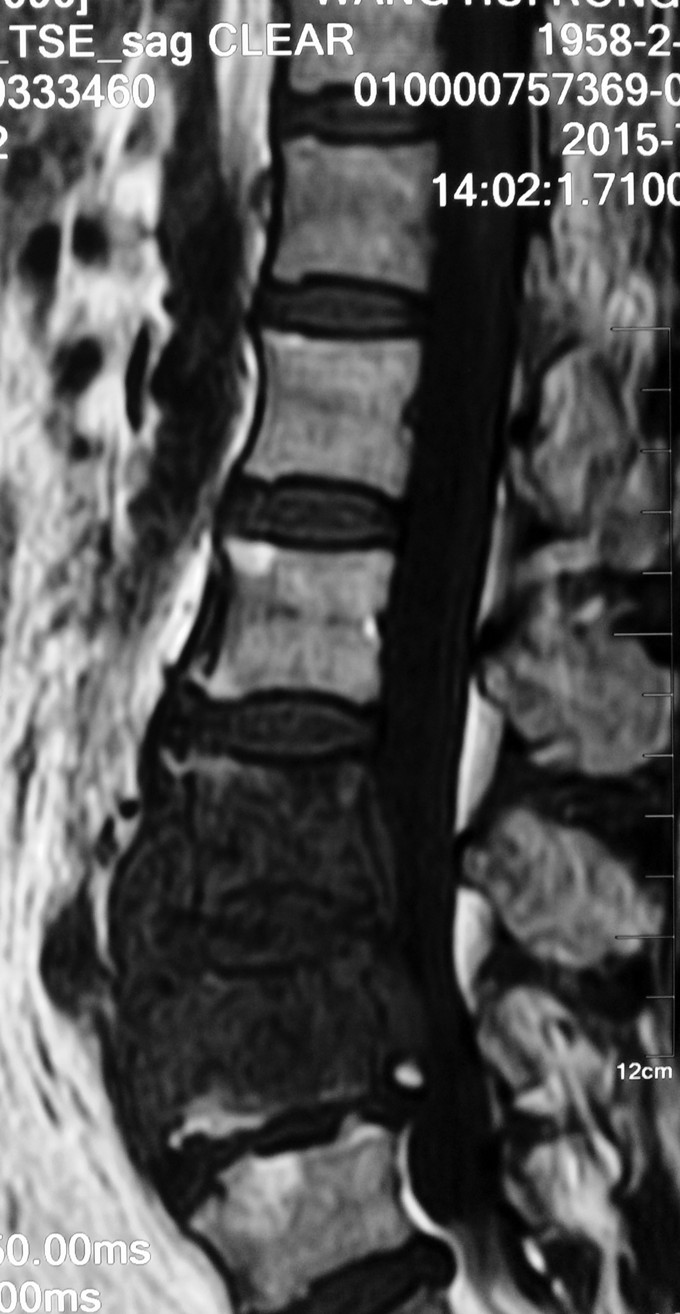

1.腰3-4结核 2.腰4-5椎管狭窄 因术前血沉比较高,所以予以HREZS抗痨治疗2周,血沉至44mm/h,患者一般情况较前好转。安排手术治疗:后路腰3-4椎间病灶清除椎板植骨+腰4-5减压植骨内固定融合术。

此患者腰椎结核伴有相邻节段椎管狭窄,所以兼有两者的症状。对于此病例我们考虑因患者椎体前方脓肿不明显,所以考虑一起行后方椎间隙病灶清除,植入自体椎板骨融合内固定,同时进行腰4-5后路减压内固定融合术。 不知大家对结核的病人一般是通过何种方式进行病灶清除的?选择原则是什么?